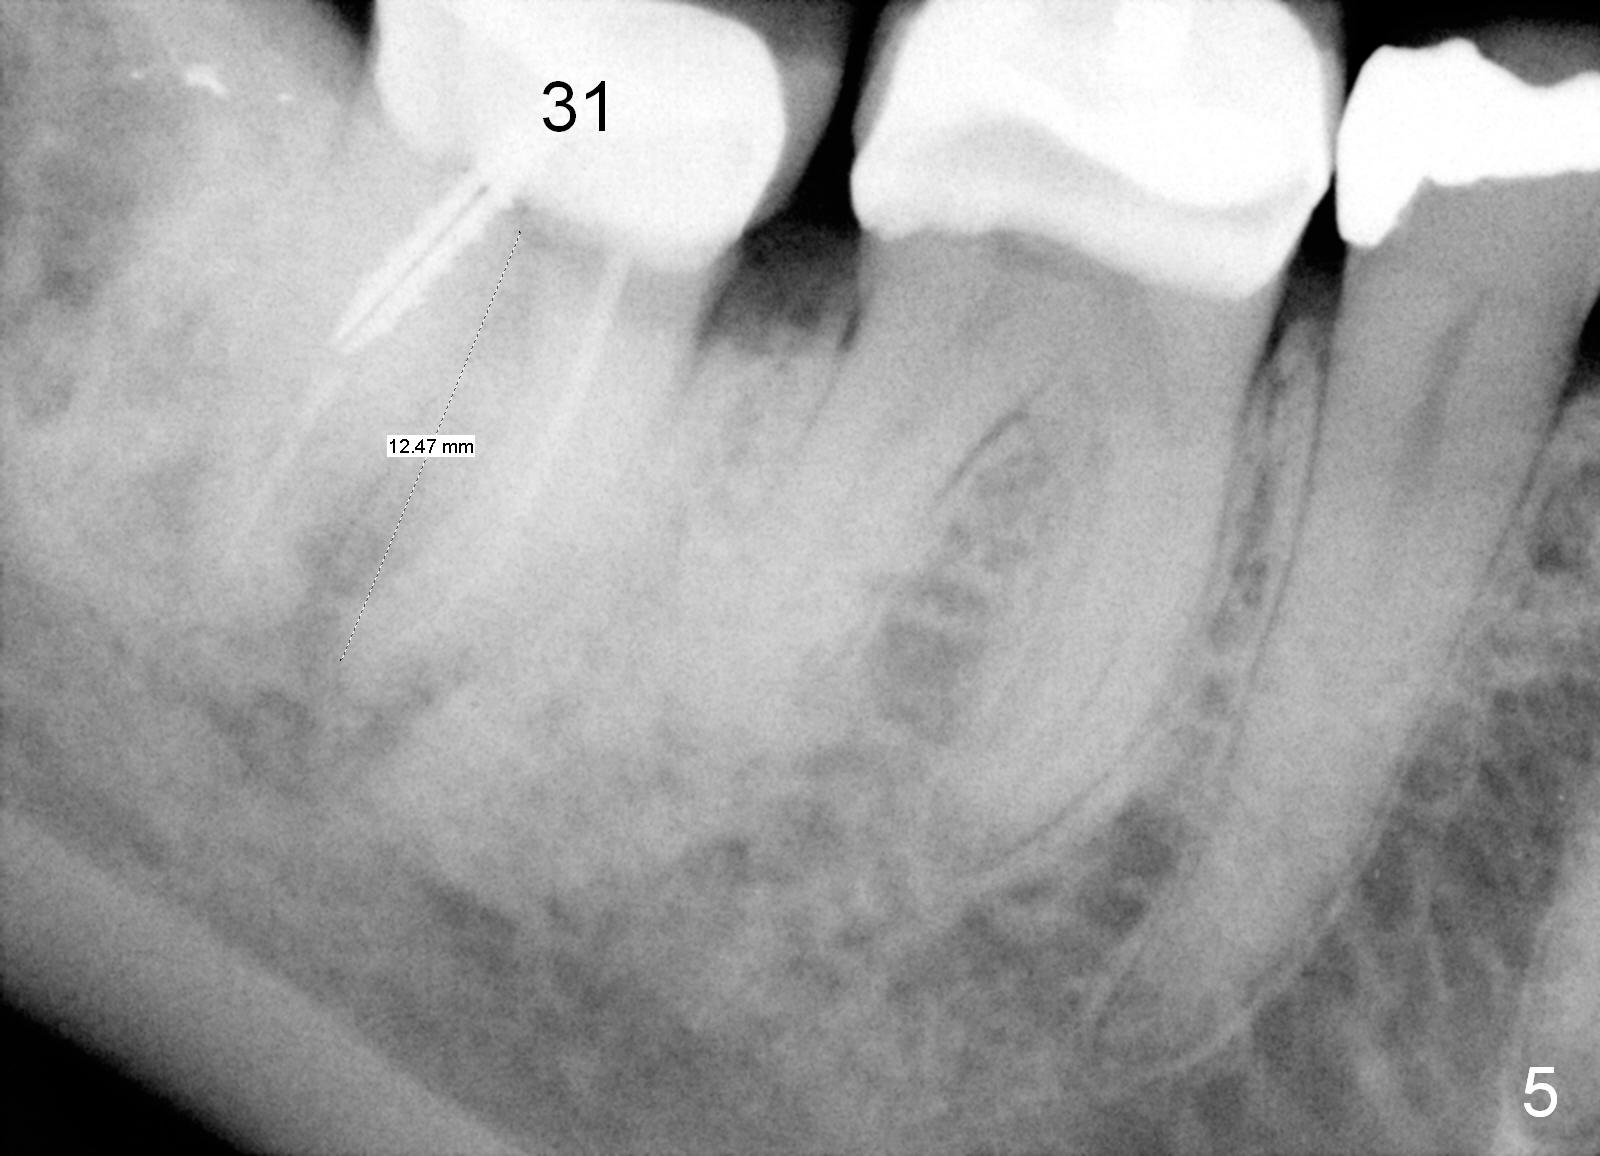

She suddenly decides to have an implant to be placed at the site of #31, 5.5 years post extraction (Fig.5). If she does not have chance to take preop CT, the initial osteotomy depth will be 8 mm. Then take the 1st intraop PA for bone height confirmation. If the bone height is <8 mm, use Master Sinus Lift Kit and SM Extra Wide Kit. Place an implant as low as possible, since the opposing tooth must have been supraerupted.